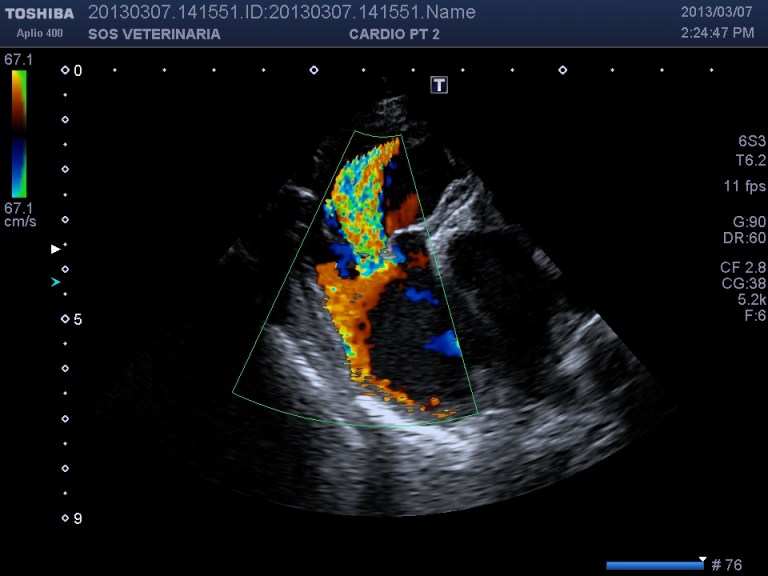

Ecco i filmati piu’ significativi osservare il flusso laminare che scorre parallelo alla parete laterale dell’arteria polmonare non piu’ continuo ma annullato in sistole dalla gittata in polmonare ,nel terzo filmato si vede l’ampolla del dotto